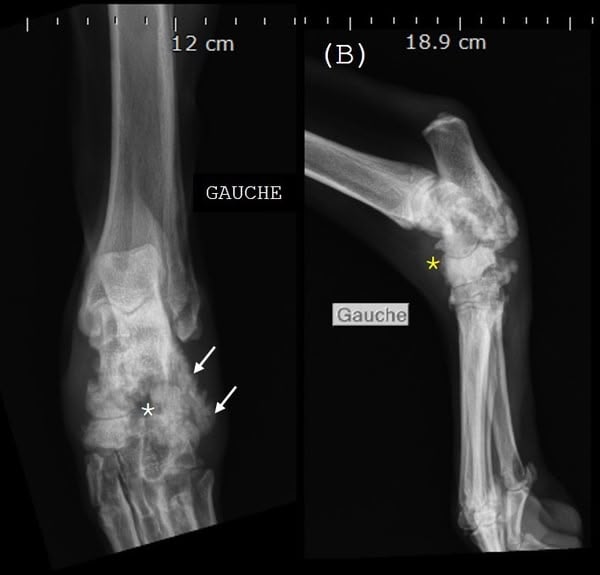

Le dernier cas de notre étude est un chat présenté pour ataxie et dont le scanner montre une fracture ponctiforme de l'os pariétal gauche du crâne avec abcès intracrânien et sous-cutané, probablement secondaires à un traumatisme. Un traitement médical est mis en place. Après une amélioration transitoire de son état général, le patient décède trois jours plus tard.